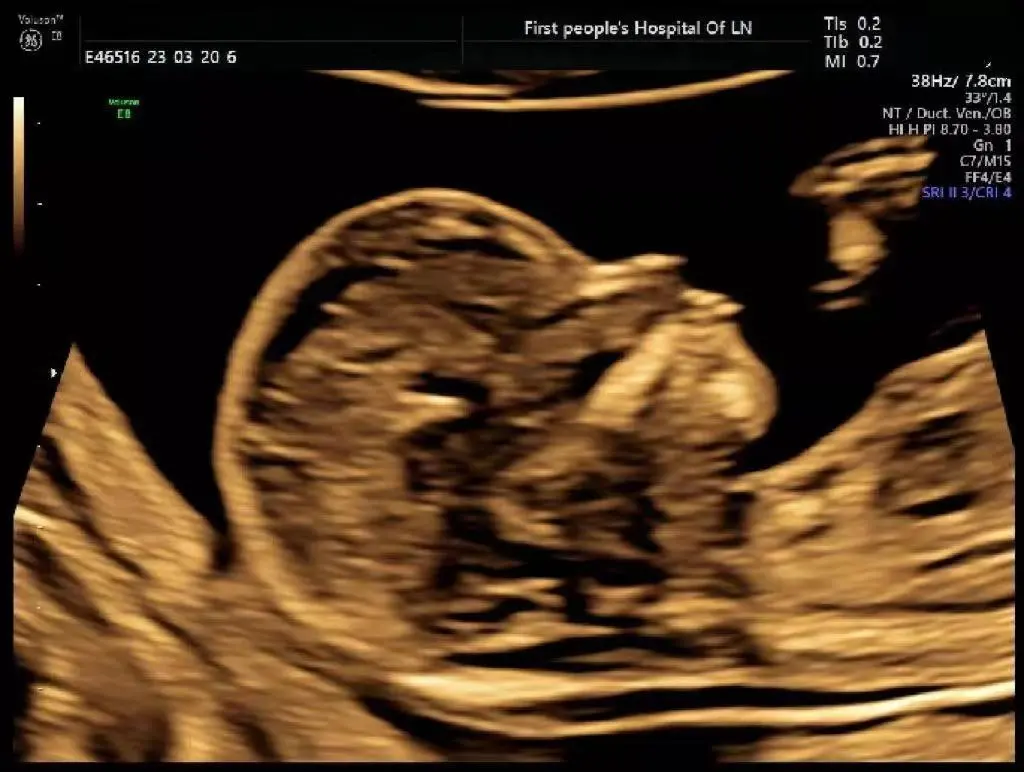

01 胎儿颈部透明带检查(NT检查)

免费为妊娠11-14周的孕妇提供一次超声胎儿颈部透明带检查(NT检查)。